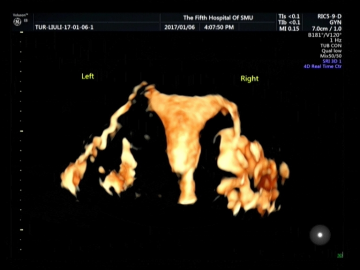

南医五院四维输卵管超声造影技术诞生

发布时间:2017-01-25 18:27:23

随着不孕妇女患者数量不断地增加以及我国二胎政策的开放,输卵管原因导致的不孕患者逐渐增多。南方医科大学第五附属医院超声医学科经过近半年的筹备,于2017年1月成功开展了第一例经阴道四维输卵管超声造影,标志着南医五院超声技术从二维平面向实时立体空间超声造影的方向取得突破性进展。 该技术利用超声造影剂(六氟化硫微泡)稳定显...